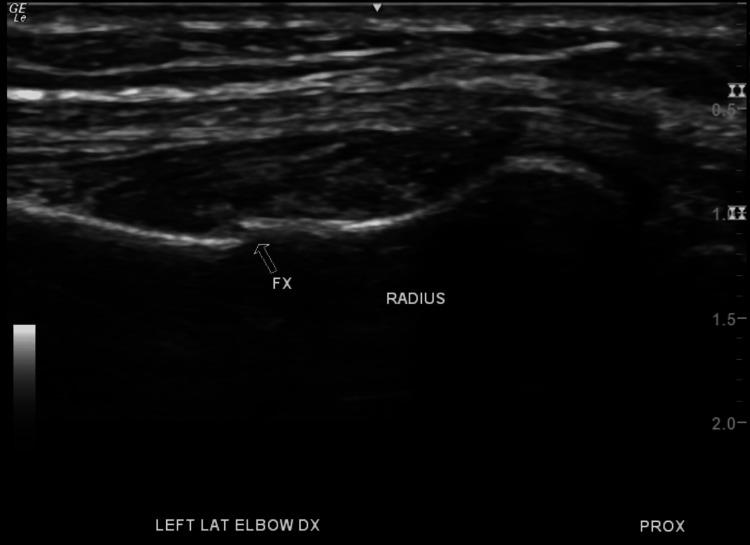

The standard convention for diagnosing bone fractures is through radiography. However, radiography can miss fractures depending on the type of injury or if human error is present. This may be due to improper patient positioning leading to superimposing bones being captured in the image, obscuring pathology. As of late, ultrasound has been gaining traction in terms of its utilization for diagnosing fractures, which radiography can miss at times. Here we present a case of a 59-year-old female who was diagnosed using ultrasound with an acute fracture that was initially missed on X-ray. We present a case of a 59-year-old female with a past medical history significant for osteoporosis who presented to an outpatient clinic for evaluation of acute left forearm pain. She reported sustaining a mechanical fall forward to the ground three weeks before bracing herself with her forearms, immediately developing left upper extremity pain lateralized to the forearm. Upon initial evaluation, forearm radiographs were obtained and showed no evidence of acute fractures. She then underwent a diagnostic ultrasound that showed an obvious fracture of the proximal radius, distal to the radial head. Upon reviewing initial radiograph films, it was evident that the proximal ulna was superimposed over the radius fracture as a proper neutral anteroposterior view of the forearm was not taken. The patient then underwent a computed tomography (CT) scan of her left upper extremity, which confirmed the presence of a healing fracture. We present a case in which ultrasound is an excellent adjunct when a fracture cannot be identified on plain film radiography. Its utilization should be well-known and considered more often in the outpatient setting.

诊断骨折的标准惯例是通过X线摄影。然而,根据损伤类型或是否存在人为误差,X线摄影可能会漏诊骨折。这可能是由于患者体位不当导致图像中出现骨骼重叠,从而掩盖了病变。近年来,超声在骨折诊断中的应用越来越受到关注,而X线摄影有时会漏诊这些骨折。在此,我们报告一例59岁女性病例,其急性骨折最初在X线检查中漏诊,但通过超声得以诊断。我们报告一例59岁女性,有骨质疏松病史,因急性左前臂疼痛到门诊就诊。她报告说,在向前摔倒并以双前臂支撑身体三周前,立即出现左上肢前臂外侧疼痛。初步评估时,拍摄了前臂X线片,未显示急性骨折迹象。随后她接受了诊断性超声检查,显示桡骨头远端近端桡骨明显骨折。在复查最初的X线片时,很明显由于未拍摄前臂正确的中立前后位片,尺骨近端重叠在桡骨骨折处。患者随后接受了左上肢计算机断层扫描(CT),证实存在愈合中的骨折。我们报告这样一个病例,当在平片X线摄影中无法识别骨折时,超声是一种很好的辅助手段。其应用应该更广为人知,并在门诊环境中更频繁地被考虑。